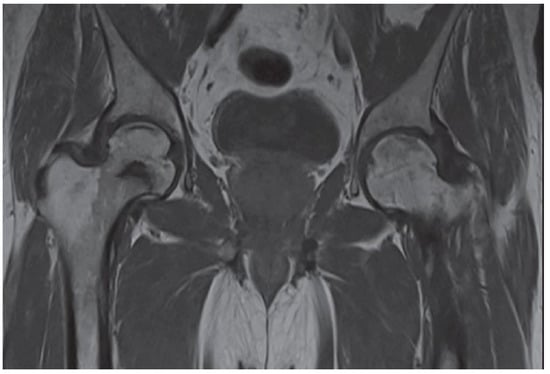

3. Clinical and Radiographic Examination of the AVN

The diagnosis of AVN is mainly based on both clinical and radiographic findings. Typical clinical presentation includes increasing pain, stiffness, and crepitus, usually proceeded by a period of minimal symptoms. During the physical examination, patients typically complain of a limited range of motion at the hip and the presence of pain, particularly with a forced internal rotation [4]. Early identification of the disease provides better outcomes. Many imaging techniques were found helpful in detecting bone necrosis signs, including X-ray, magnetic resonance imaging (MRI), computed tomography (CT), and radionuclide examinations. Imaging evaluation of AVN should begin with radiography, a non-expensive and widely available technique. Classic radiography may show subchondral radiolucency, called the “crescent sign”, indicating subchondral collapse [9]. CT and X-ray are less sensitive than MRI and show the necrotic changes during later stages of AVN. Nonetheless, signs of AVN are often apparent enough not to warrant additional radiologic evaluation [43]. Typical findings on MRI in a patient with an AVN are pictured in Figure 3.

MRI is the gold standard for osteonecrosis diagnosis and allows differentiating AVN from other diagnoses that may mimic it, such as bone bruises or transitioned osteopenia [1,9]. MRI allows for early AVN diagnosis and may help identify patients at risk of femoral head fracture. Identification of bone marrow edema in the proximal femur and joint effusion are critical prognostic factors [3]. T1-weighted images show a limited subchondral linear-shaped low signal intensity, while T2 demonstrates a double-line sign [44]. However, MRI cannot be used after fracture fixation with metallic implants, limiting its utility, especially in patients who develop bone ischemia following surgical procedure [18].

Figure 3. The posteroanterior view shows a right (R) AVN of the femoral head (T1-weighted).